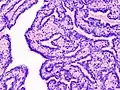

Histopathology of intraductal papilloma of the breast by excisional biopsy. Hematoxylin and eosin stain.